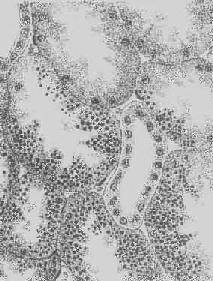

肝淀粉样变

图1-22 肝淀粉样变

淀粉样物质呈均质状,沉着于窦内皮下,肝细胞索受压萎缩

5.淀粉样变性 组织内有淀粉样物质沉积称为淀粉样变性(amyloid degeneration,amyloidosis)。淀粉样物质为一种结合粘多糖的蛋白质,遇碘时被染成赤褐色,再加以硫酸则呈蓝色,与淀粉遇碘时的反应相似,故称之为淀粉样物质。此物质常浸润于细胞间或沉积于小血管的基底膜下,或沿网状纤维支架分布(图1-22)。淀粉样物质在HE染色切片中为淡红色均质状,电镜下则为纤细的丝状。

淀粉样变可为全身性和局部性二种。前者在我国极为罕见,多发生在长期慢性化脓、骨髓及结核病等情况下。局部性淀粉样变则较常见,并好发于睑结膜及上呼吸道等处的慢性炎症而伴有大量浆细胞浸润时,发生机制不清。根据淀粉样物质中常有丙种球蛋白和血清中球蛋白增多的现象,有人认为这是由于抗原抗体反应在血中形成的蛋白复合物,也有人认为是浆细胞产生的免疫球蛋白与纤维母细胞、内皮细胞所产生的含硫粘多糖相结合而形成的复合物。